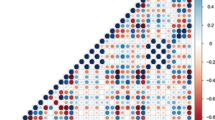

To construct the radiomics model, the z-score method, suitable for normalizing radiomics parameters with different magnitude orders, was adopted to improve the homogeneity of all radiomics features [39], among which variables with ICC > 0.8 were used to screen further. The least absolute shrinkage and selection operator (LASSO) with 10-fold cross-validation was conducted for determining the subset of features with the best λ, and then building the radiomics model by backward stepwise multivariate logistic regression.

After applying LASSO selection, the pancreatic features with ICC over 0.8 were reduced to ten variables (Fig. 2), which were further simplified into five to construct the pancreatic radiomics model by backward stepwise multivariate logistic regression.

Radiological texture features selection utilizing the least absolute shrinkage and selection operator (LASSO) algorithm and 10-fold cross-validation. a Optimal parameter (λ) selection in LASSO model used cross-validation via minimum criteria. Dotted vertical lines were drawn at the optimal values by using the minimum criteria and 1 standard error of the minimum criteria (the 1-SE criteria). A λ of 0.016 with log (λ) = -4.135 was chosen. b LASSO coefficient profiles of the 37 radiomics features with ICC > 0.8. A coefficient profile plot was generated versus the selected log(λ) value, where 10 features with nonzero coefficients were chosen